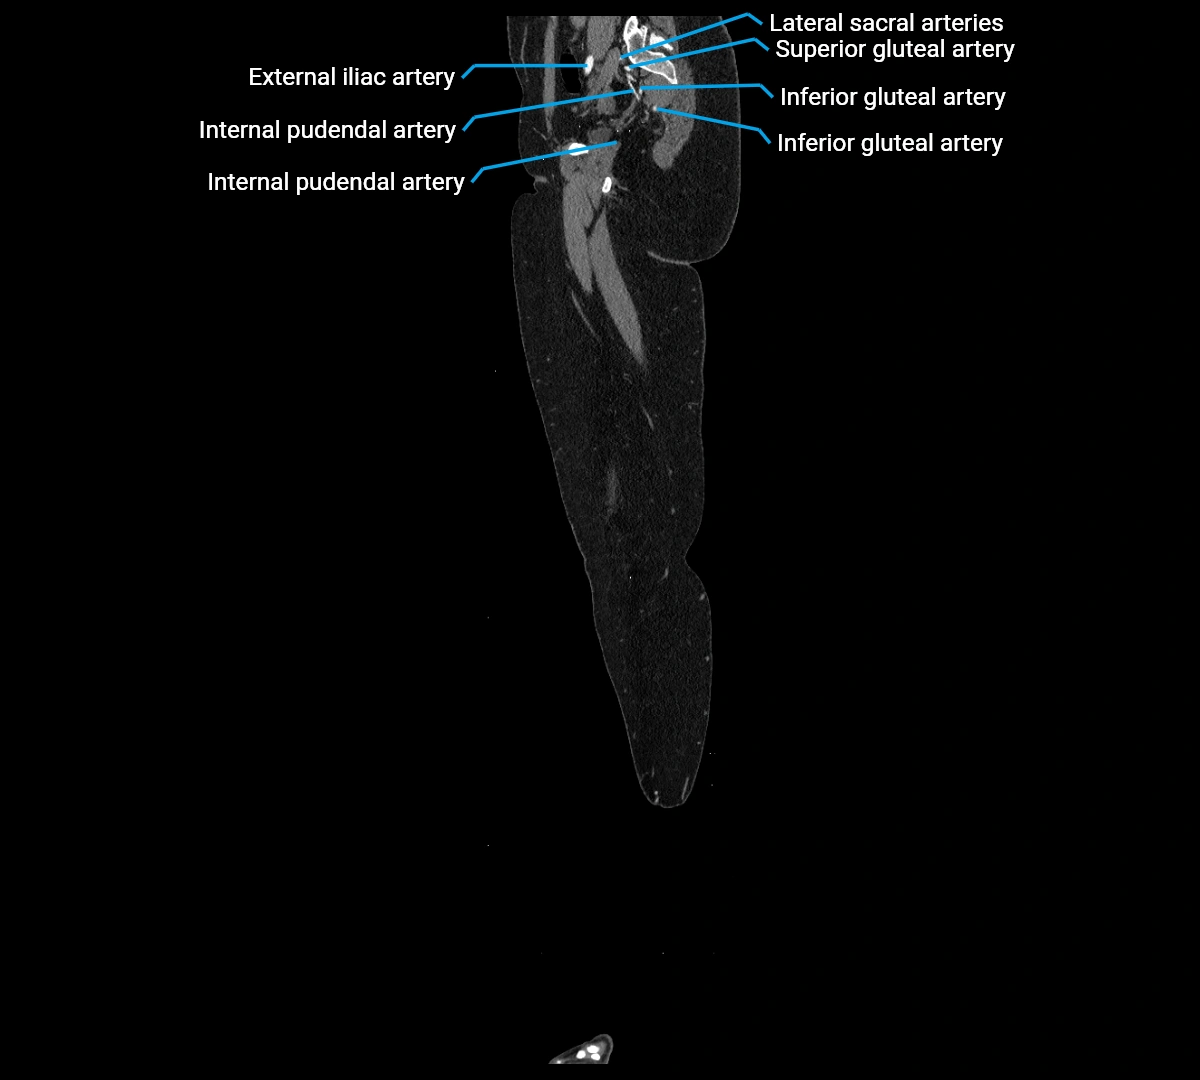

CT Appearance

Non-contrast CT:

• Appears as a tubular soft tissue structure anterior to vertebral bodies

• Calcified atherosclerotic plaques appear as hyperdense foci along the wall

• Useful for screening abdominal aortic aneurysm (AAA) size and mural calcification

Contrast-enhanced CT (CTA):

• Gold standard for abdominal aortic imaging

• Provides excellent detail of lumen, wall, aneurysm, thrombus, and branch vessels

• Multiplanar and 3D reconstructions help in aneurysm measurement, stent graft planning, and dissection evaluation

• Detects acute rupture, traumatic injury, or occlusion with high sensitivity